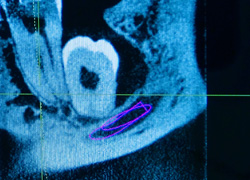

Allerdings bieten wir hier auch die Option einer kompletten digitalen 3D Planung an.